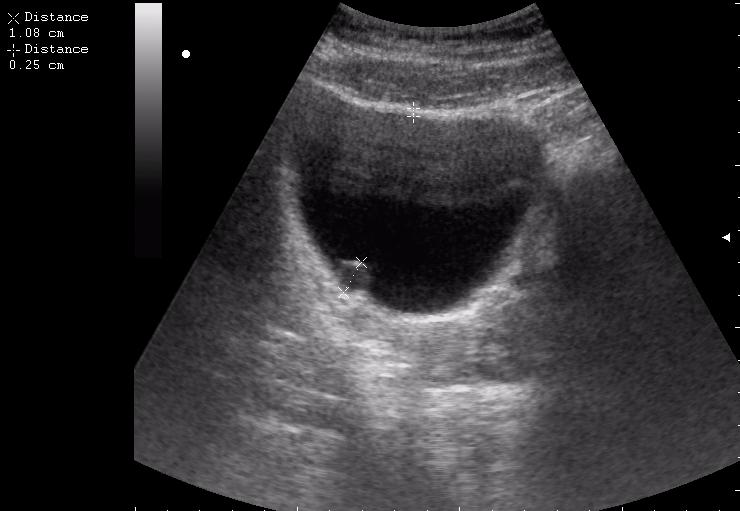

Сравните

Продольное сканирование мочевого пузыря После легкой перкуссии мочевого пузыря

зато какое наполнение! а осадок убедительный! а же не 7-кой смотрела!На сонограммах неубедительно продемонстрирован осадок да и стенки м.п. не утолщены.